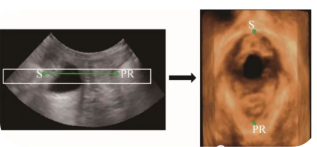

您是否也遇到过这些尴尬时刻?提重物时突然漏尿、运动时总觉下腹坠胀、更年期后总想跑厕所......这些信号可能在提醒:盆底肌需要关爱了。 盆底肌群如同"弹簧床",承托着膀胱、子宫等器官。妊娠分娩、雌激素变化、长期腹压增加等因素,都可能导致这张"网"松弛。若不及时干预,可能发展为: ▷ 盆腔器官脱垂(子宫/阴道膨出) ▷ 压力性尿失禁(咳嗽/大笑漏尿) ▷ 排便障碍(便秘/失禁) ▷ 性生活质量下降 【哪些人需要关注盆底筛查?】 ✓ 产后42天妈妈(尤其经阴道分娩) ✓ 频繁漏尿或排尿困难 ✓ 长期便秘/慢性咳嗽 ✓ 更年期女性 ✓ 性生活疼痛或下腹坠胀人群 【无创筛查新选择:盆底超声】 不同于传统指检,这项技术通过会阴体表扫描: ⏩ 多维度观察静息/收缩/用力状态 ⏩ 精准评估肌群损伤程度 ⏩ 动态捕捉器官位移情况 女性盆底三维多层显像 【检查须知】 ✔️ 避开经期 ✔️ 检查前排空膀胱 ✔️ 穿宽松裤装更方便 ✔️ 配合医生指令做缩肛/屏气动作 盆底超声检查 女性健康管理不该止于体检常规项。建议存在相关症状的女性,及时到正规医院妇产科或超声科咨询。早筛查、早干预,让盆底肌恢复应有的"托举力"。 注:部分图片来源于网络,如有侵权,请联系删除。 贵州航天医院超声科专家团队 吴艳辉 中共党员,超声科学科带头人、主任,主任医师 专业擅长:从事超声诊断工作约30年,对心血管、小器官超声、超声引导下介入等具有丰富的临床经验。 胡大海 超声科副主任,副主任医师 专业擅长:从事超声工作17年,对心血管、外周血管、浅表器官超声诊断等具有丰富的临床经验。 骆科美 中共党员,超声科副主任医师 专业擅长:从事超声诊断工作33年,对胎儿心脏及颅脑、妇产超声诊断、盆底超声等诊断具有丰富的临床经验。 刘 敏 超声科副主任医师 专业擅长:从事超声诊断工作20余年,对妇产科超声、心脏血管超声诊断具有丰富的临床经验。 贵州航天医院超声科简介 基本情况 贵州航天医院超声科配备多种超声检查设备(飞利浦彩超(IU-22、IU-Elite、HD11、Q5、Q7),迈瑞超声I9、DC-6、DC-8、GE-E8及床旁机,彩色超声诊断仪等),设有心血管诊室、妇产科诊室、腹部诊室、绿色通道、浅表小器官等检查室。 诊疗范围 科室业务覆盖腹部、泌尿、妇科、产科(常规、NT筛查、III级筛查超声检查及高危妊娠监护)、成人心脏、外周血管、浅表器官(包含甲状腺、乳腺、阴囊、眼睛等)、颅脑(小儿颅脑、成人颅脑)、小儿肺超、造影、盆底、腹直肌、肌骨神经等检查及各种介入引导。 专科特色 四肢血管超声检查、双胎产前筛查及超声监护、超声造影检查技术、介入超声临床应用、经颅脑实质超声辅助筛查诊断帕金森病、女性性早熟超声诊断、盆底超声检查等。 NT超声检查 超声介入引导 肝脏超声造影 甲状腺造影 颅脑超声帕金森辅助检查 乳腺超声造影 上肢动静脉造瘘超声检查 双胎超声筛查 下肢血管超声检查 右心造影 END